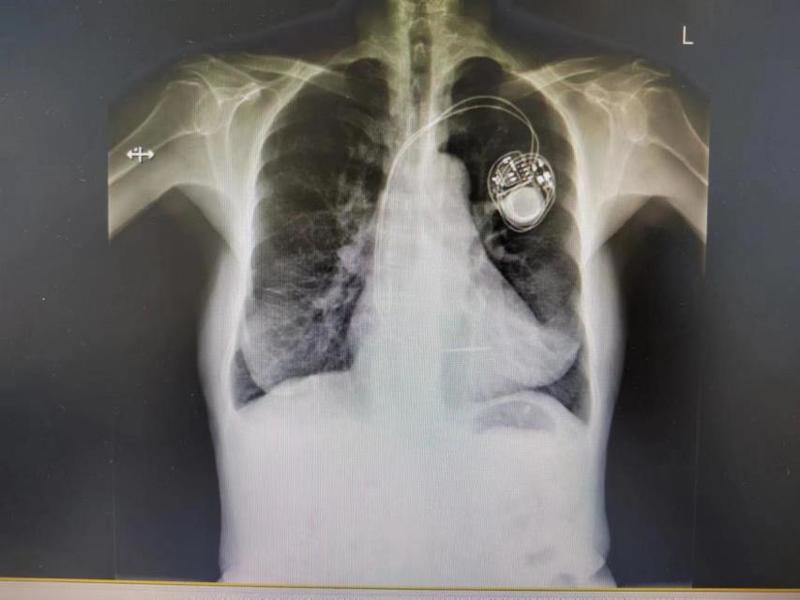

▲起搏器图像

刘阿姨长期患有肺病,桶状胸明显,加之营养缺乏,体重仅有35kg,这些都为手术增加难度。手术当天,赵宏伟治疗组为刘阿姨实施了起搏器植入手术,仅用时1小时零5分钟。术中起搏器电极位置佳,各项参数良好,刘阿姨也感觉到从来没有过的轻松。术后再次行起搏器程控,提示各项指标均满意,切口愈合良好。近日,刘阿姨已经顺利出院。